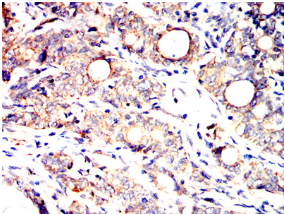

| AC3515 | SLC2A14 Mouse Monoclonal antibody[8E10E] | 100ug | $367 | 10days |

| AC3515 | SLC2A14 Mouse Monoclonal antibody[8E10E] | 200ug | $660.6 | 10days |